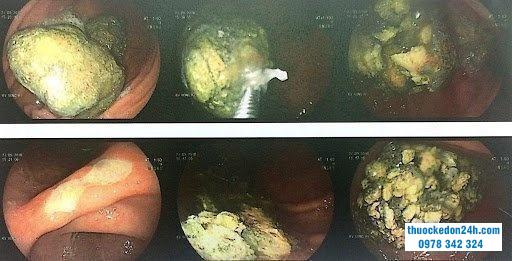

Hình ảnh gắp bã thức ăn dạ dày nhờ nội soi

Thủ thuật nội soi được thực hiện để chẩn đoán đồng thời loại bỏ bã thức ăn ra ngoài. Các bước tiến hành gồm:

Đưa ống overtube (ống nhựa cứng) qua máy soi để đảm bảo khi lấy dị vật ra không gây tổn thương ống tiêu hóa.Tiến hành nội soi dạ dày theo quy trình nội soi tiêu hóa được Bộ Y tế ban hành. Ống nội soi sẽ được đưa từ từ vào miệng, hình ảnh đầu dò sẽ truyền tới màn phép bác sĩ quan sát và đánh giá. Thòng lọng được sử dụng để cắt nhỏ từng phần cục sau đó, dùng rọ gắp dần kéo ra ngoài qua đường miệng bằng cách kéo cả dây máy nội soi ra ngoài đôi rất khó cắt.